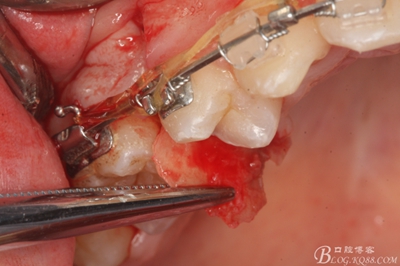

圖12. 做垂直切口+齦溝內(nèi)切口,形成角形瓣,暴露出15根面。

圖13. 用小球鉆去除約1mm牙槽骨,暴露15牙根面約5mm。